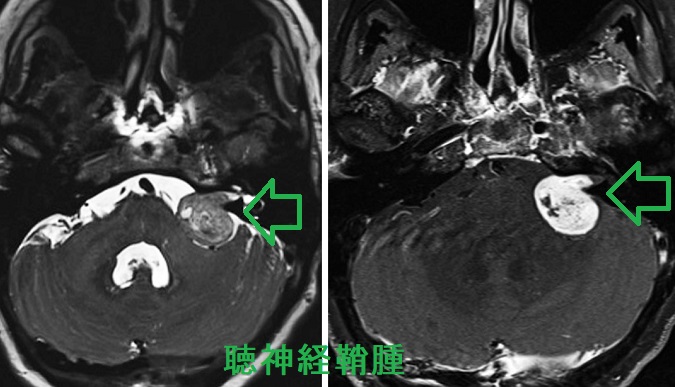

もっとも頻度が高い神経鞘腫(シュワノーマ)は聴神経腫瘍です。聴神経腫瘍の症状は

- 耳鳴・聴力低下(蝸牛神経障害)

- めまい、ふらつき(上前庭神経、下前庭神経障害)

- 顔面神経麻痺(顔面神経と聴神経は並走しているため)

などです。

これらの症状がある場合や、腫瘍が大きく脳を圧迫している場合は

- 手術摘出+残存腫瘍にサイバ-ナイフ、ガンマナイフの放射線治療

- 放射線治療のみ

聴神経は非常に脆いため、術後の麻痺を考えた上でどちらにするのか決めます。

また、術後顔面神経麻痺を来す場合もある。多くは一時的だが、永続性の場合は再建手術も。

聴神経鞘腫に次いで多いのが三叉神経鞘腫で、舌下神経鞘腫もある。